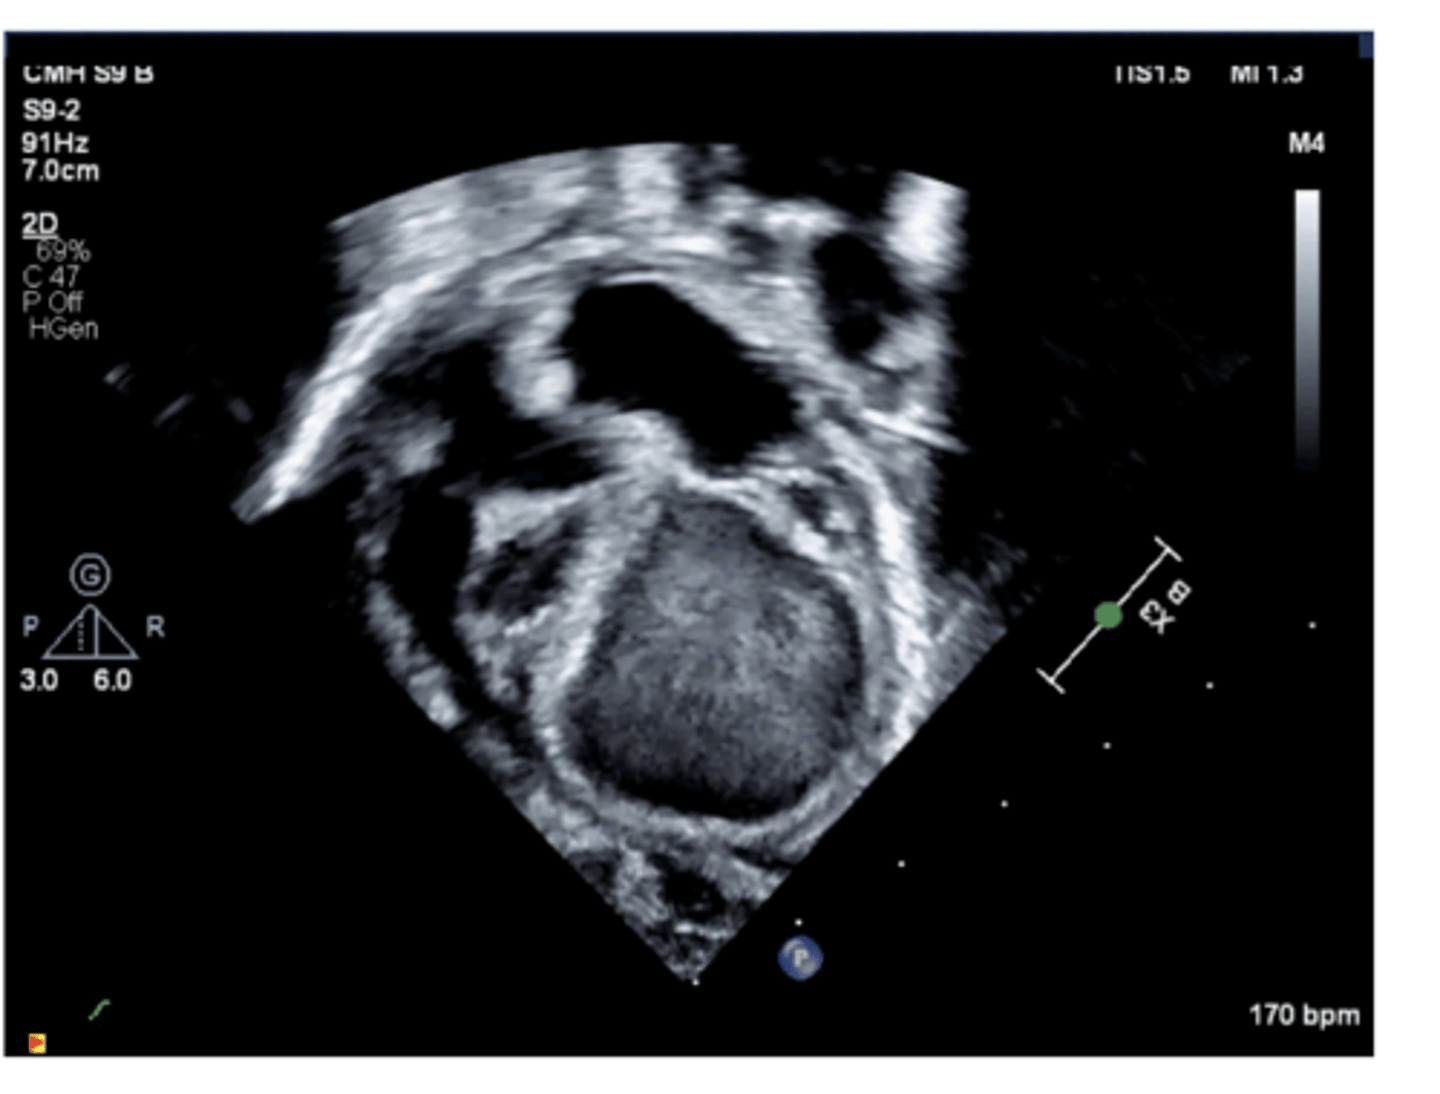

critical AS

WHAT LESION?